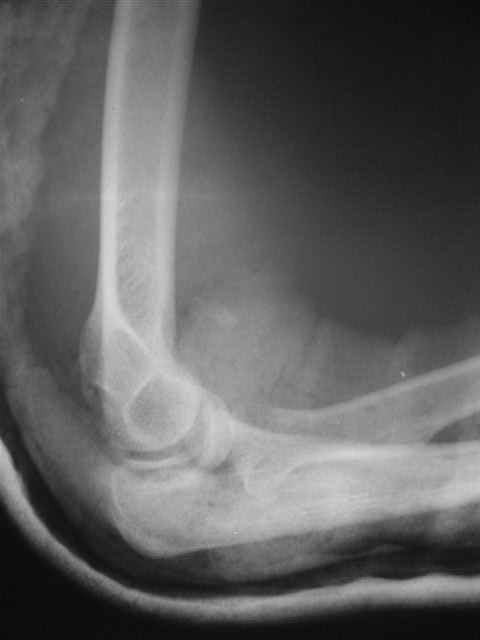

Re: Вывих костей предплечья и перелом головки луче

Вы указали последствия резекции головки луча: нестабильность, вальгусная деформация, влияние на дистальное радиоульнарное сочленение, поэтому при изолированных или сочетанных повреждениях гоовки, стараюсь ее *собрать*, фиксируя межфрагментарными 1,5 - 2,0 мм винтами, по ситуации + L-пластиной. Отмечается ограничение амплитуды ронации-супинации впоследствии, но локтевой сустав остается стабильным. Результаты протезирования головки флотирущими имплантами функционально удовлетворительны и применительны к случаям, когда *собрать* мнооскольчатый перелом невозможно.